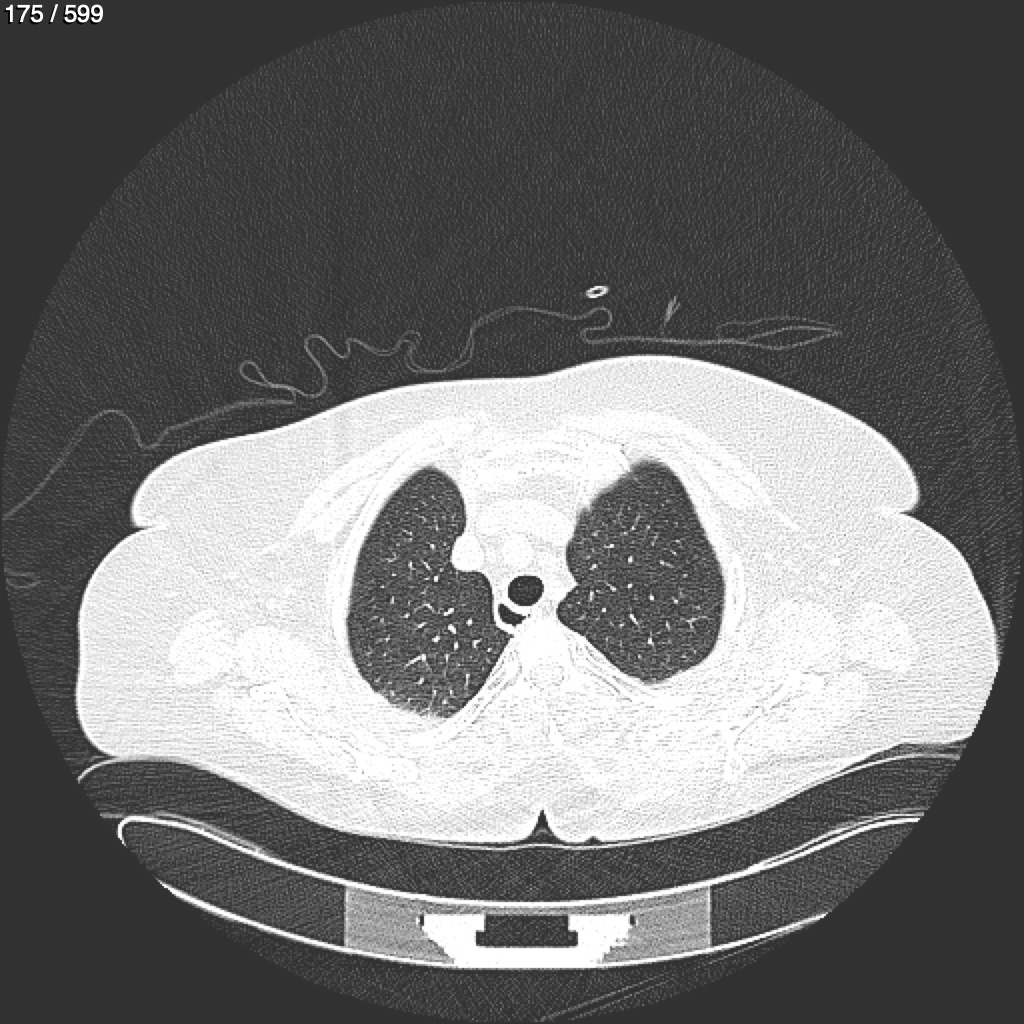

Home G​l​o​r​i​a​ ​G​l​a​d​y​s​ ​B​e​a​s​l​e​y​ ​-​ ​T​ó​r​a​x​ ​T​o​r​a​x​_​S​i​m​p​l​e​ ​(​A​d​u​l​t​o​)